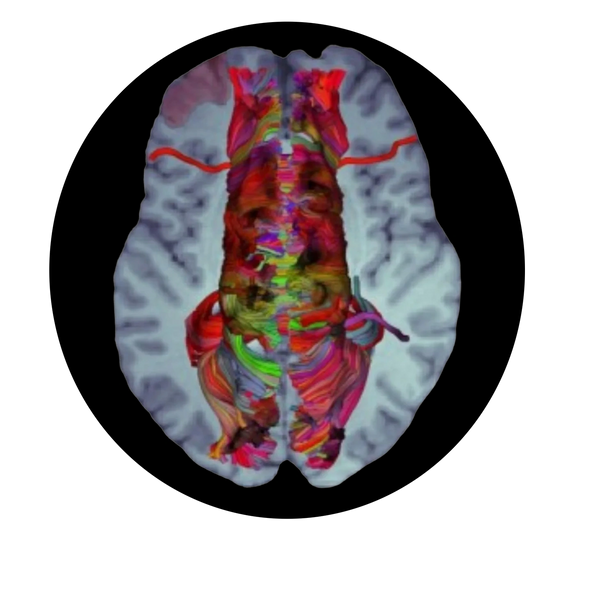

Our solution provides high-precision analytics tools that integrates AI models and advanced algorithms to simplify the landscape of complex brain surgery. During neurosurgery nerve damage is one of the most common causes of neurological deficit which accounts for 41% while 6% (Acta Neurochirurgica, 2020, 162:3005–3018) remains as permanent deficit leading to disability adjusted life years (DALYs) for the patient.